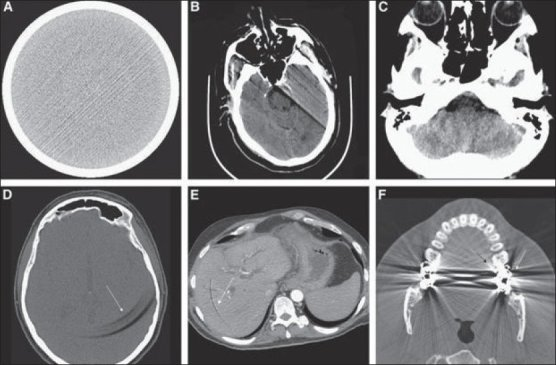

Then come the artifacts. Patients move and breathe; implants reflect rays and bloom; noise changes with the scanner and protocol; contrast phases alter how tissue appears; rings and beam-hardening artifacts appear when you least want them. If you train only on clean slices, the first busy day on the ward will cause the model to appear lost.

(A) Streak (B) Motion (C) Beam-hardening (D-E) Ring (F) Bloom